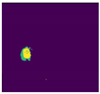

| Test Case | 1 | 2 | 3 | 4 | 5 |

|---|---|---|---|---|---|

| Image | ![]() | ![]() | ![]() | ![]() | ![]() |

| Ground Truth | ![]() | ![]() | ![]() | ![]() | ![]() |

| Segmented Region | ![]() | ![]() | ![]() | ![]() | ![]() |

| Result | Fail | Pass | Fail | Pass | Pass |